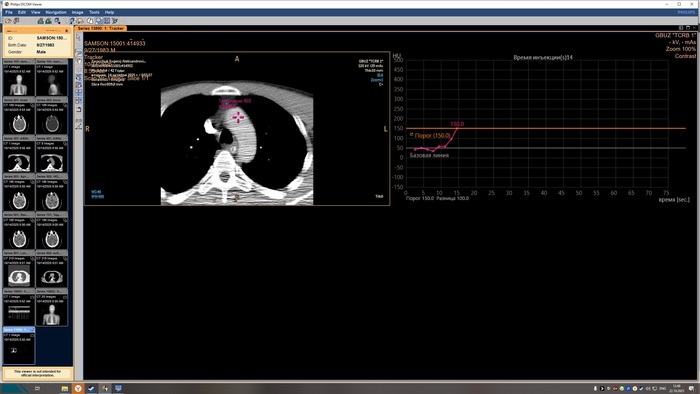

Описание КТ прикрепляю, а снимки будут в конце поста, по-другому у меня не получилось.

Снимки КТ